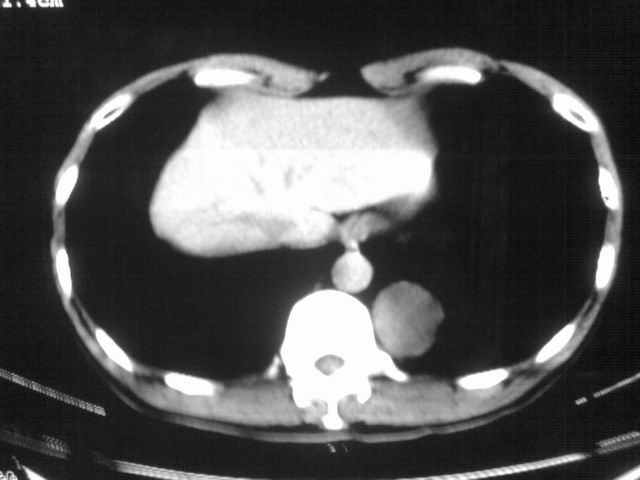

以下是引用苯小孩在2007-4-24 19:46:00的发言:[br]左下肺内侧基底段,见类圆形病灶,边缘清晰光滑.强化后轻中度强化.<平扫第4层面似有从腹主动脉相连血管影,可惜强化扫描这层没有抓住>考虑:左下肺隔离症.建议dsa或薄层强化重建观察.

以下是引用同在2007-4-24 20:11:00的发言:[br]考虑肺隔离症